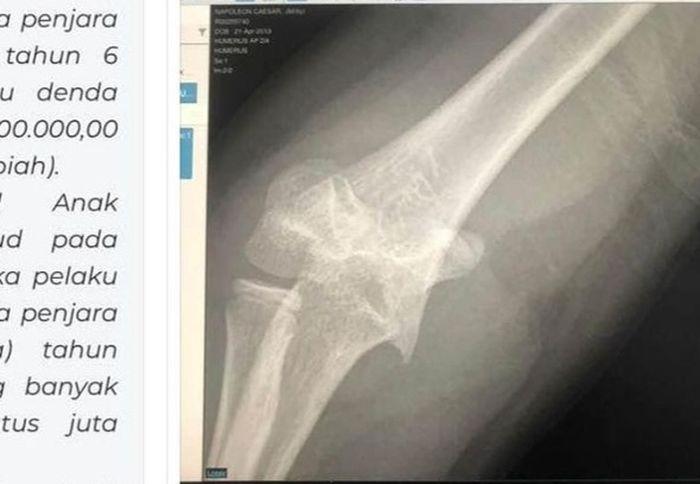

TRIBUNPRIANGAN.COM, SUKABUMI - Viral anak sekolah dasar (SD) swasta di Kota Sukabumi diduga jadi korban bullying hingga mengalami luka patah tangan di bagian kirinya.

Korban yang bersekolah di SD berlokasi di Kecamatan Cikole, tersebut mendapat penganiayaan fisik diduga oleh teman sekelasnya.